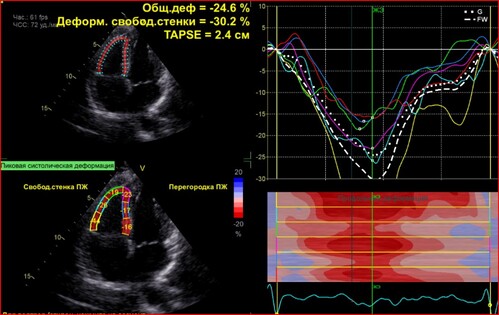

Лекция посвящена проблеме оценки систолической и диастолической функций правого желудочка.

Мы обсудим все способы расчета фракции выброса правого желудочка, способы оценки диастолы правого желудочка, причины их нарушения.

Особый интерес вызывают больные с клинической картиной правожелудочковой недостаточности. Обсудим особенности оценки этой категории больных с помощью нашего метода.

Проблема эхокардиографической диагностики инфаркта правого желудочка стоит актуально в отделениях реанимации. Уделим ей особое внимание.